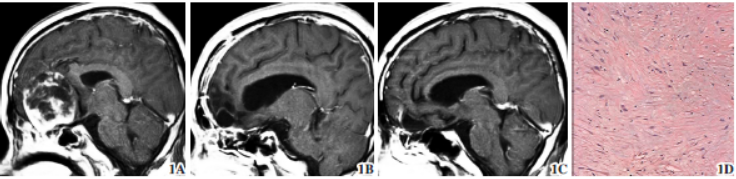

病例1(图1):男性,31岁;因“嗅觉进行性减退8年,反复肢体抽搐1天”入院。入院查体:双侧瞳孔等大,对光反射灵敏,视野尚正常。肌张力正常,左侧肢体肌力Ⅳ级,右侧肢体肌力Ⅴ级。头颅CT示右额叶类圆形占位,呈等、低密度,无钙化,未见骨质破坏。

头颅T1WI示病灶呈低、等信号,T2WI为不均匀高信号,呈不均匀强化。鼻咽、头颈部MRI检查

未见鼻部侵犯及淋巴结转移。术前诊断:右侧嗅沟巨大脑膜瘤

免疫组化显示神经元特异性烯醇化酶、突触素及嗜铬素A、S-100蛋白呈阳性表达,Ki-67指数为10%。术后诊断为右侧嗅神经母细胞瘤

(olfactory neuroblastoma,ONB),术后1周复查头颅MRI示肿瘤全切,视交叉受压得到缓解,无颅内积气及脑脊液鼻漏等并发症,病人术后视物模糊、肢体抽搐均明显改善,但嗅觉减退未好转。术后随访3年,头颅MRI检查未见复发。

图1 男性右侧ONB。1A 术前MRI T1WI 示额底肿瘤不均匀强化,基底位于嗅沟上,向后推挤视交叉;1B 术后T1WI示肿瘤全切除;1C 术后3年T1WI示肿瘤未复发;1D 病理示肿瘤细胞呈多灶状分布,其间有结缔组织分隔(苏木精-伊红染色× 100)